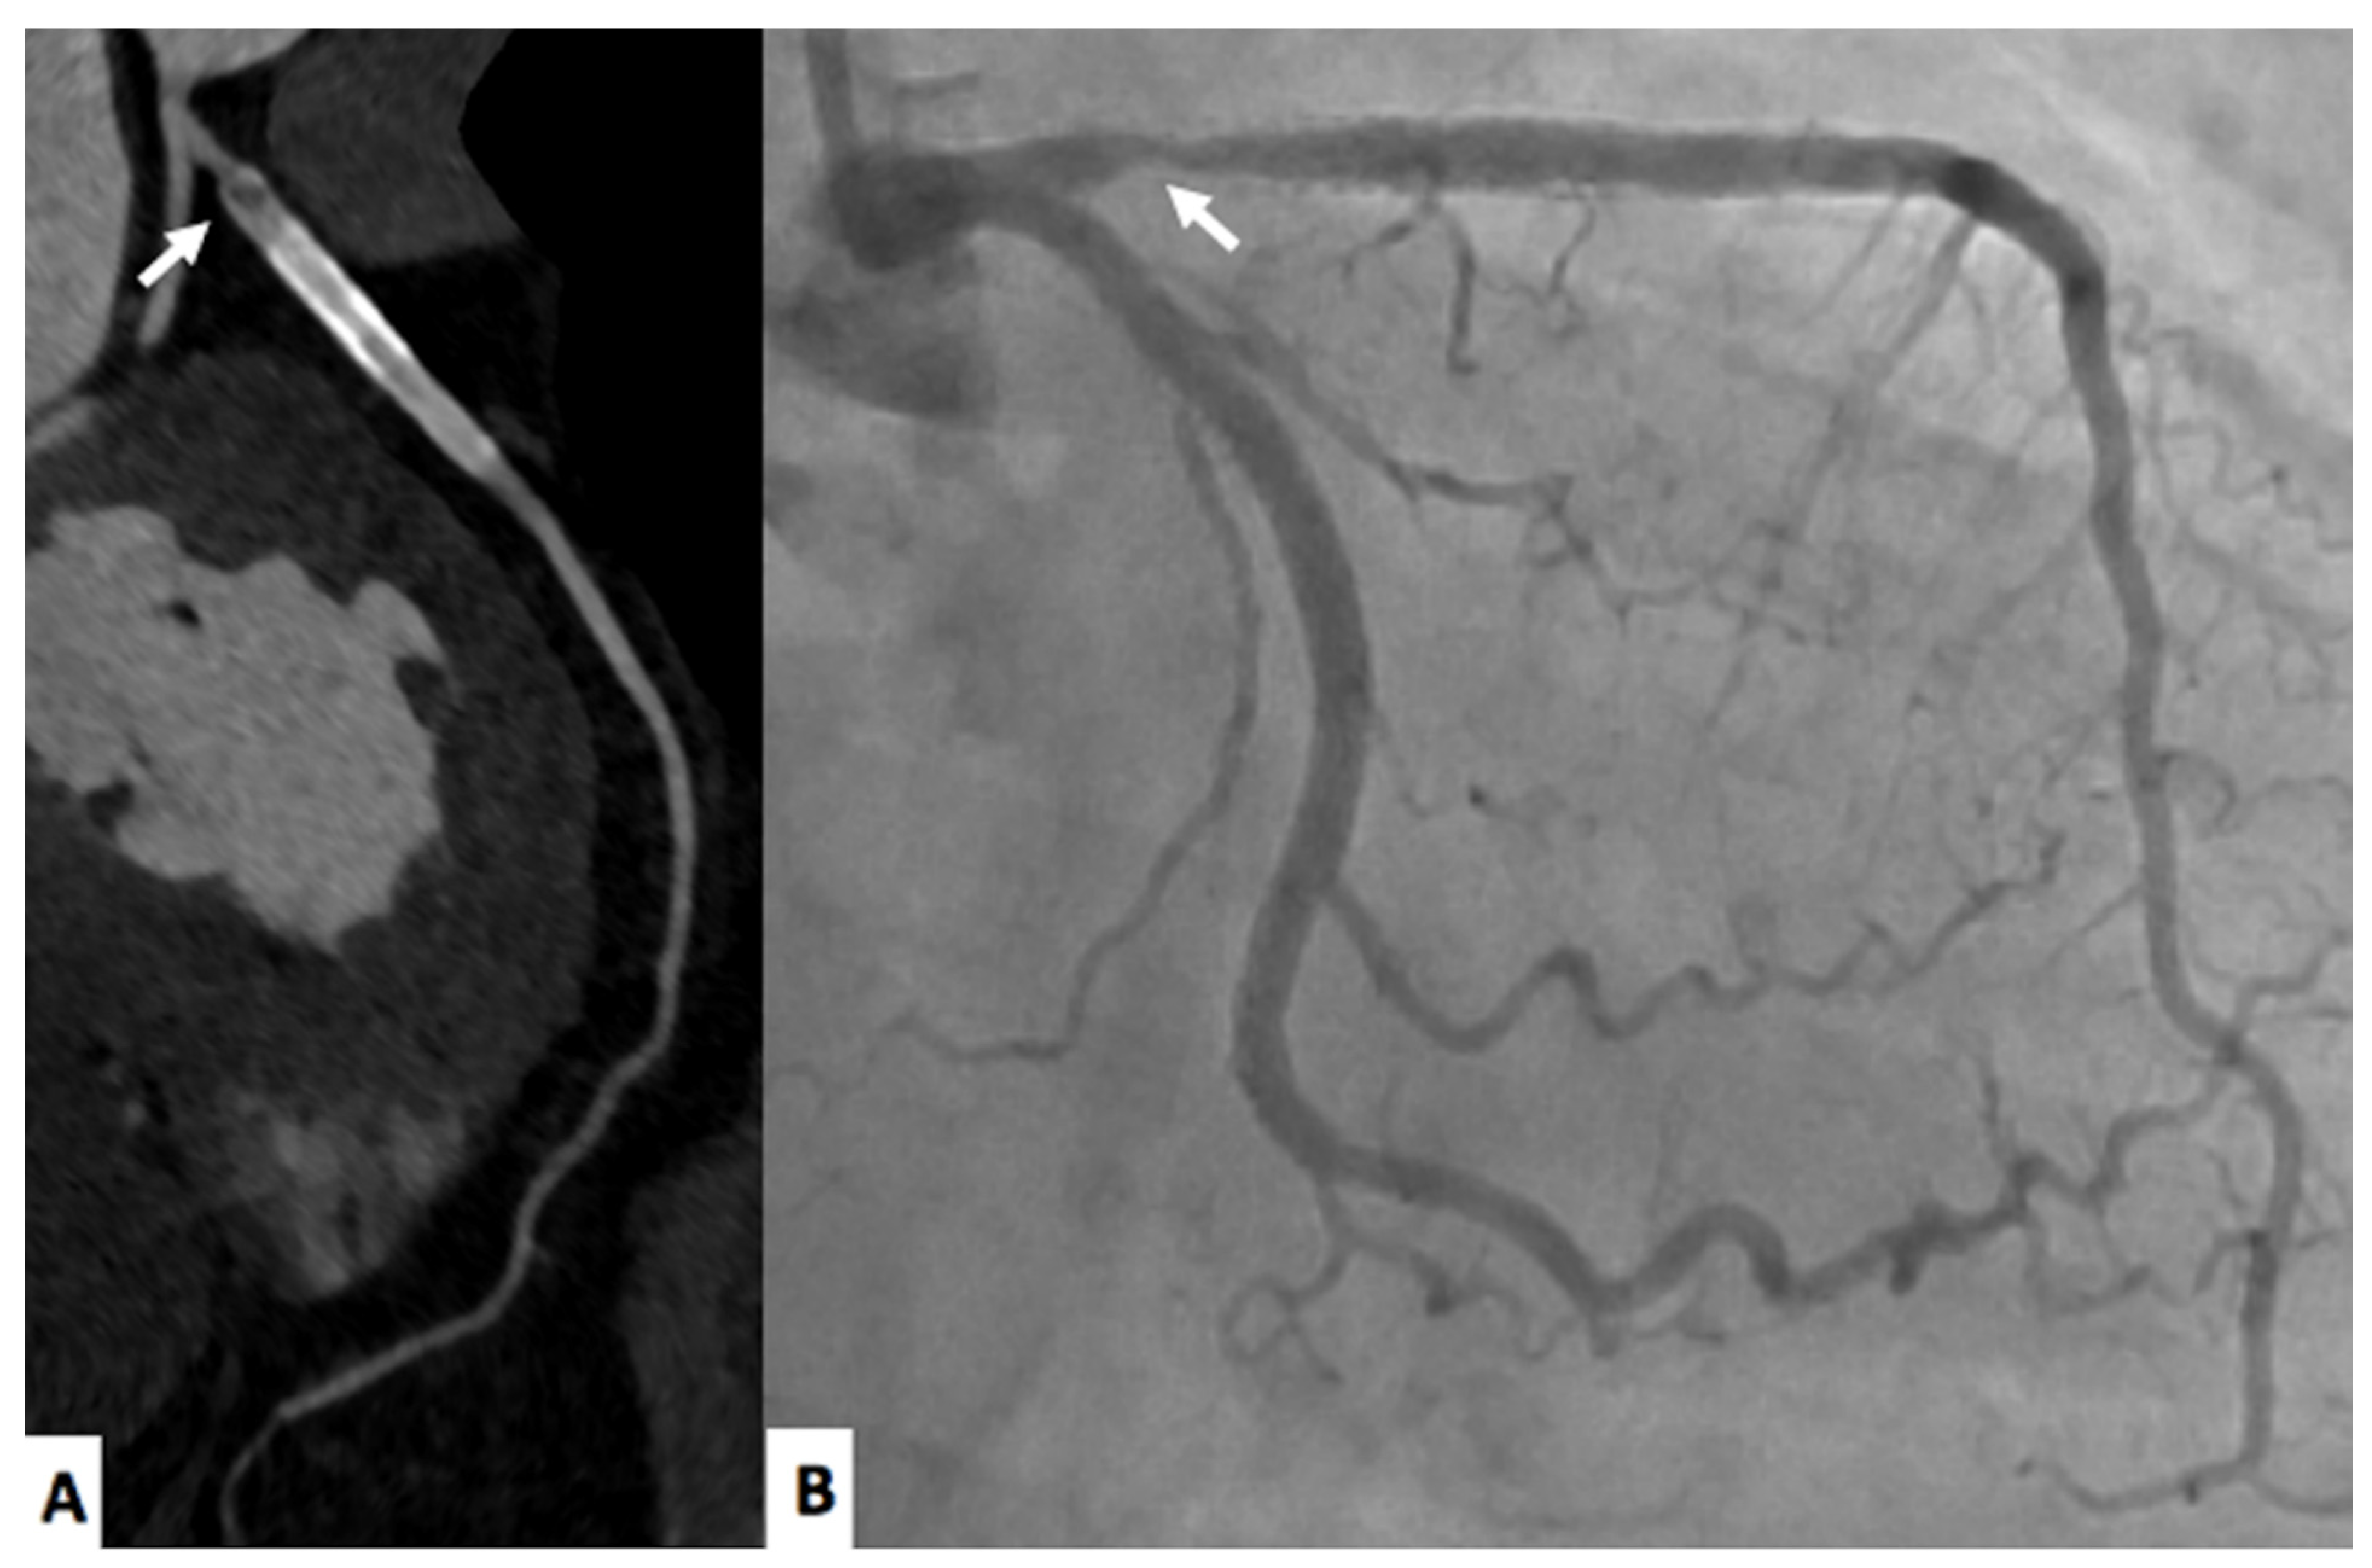

Follow up of intrastent restenosis (ISR) can be extremely difficult but still feasible with CCTA [23]. In particular, due to beam hardening artifacts, it is not uncommon to report false positive results and to send patients to invasive coronary angiography (ICA) considering that beam hardening artifacts is considered significant ISR [23]. However. the new generation CT scanners are improving the possibility of evaluating significant ISR [24,25] increasing the diagnostic accuracy due to higher temporal and spatial resolution [25]. A representative case is shown in Figure 1.

Figure 1.

A 77-year-old male with in-stent restenosis in the proximal segment of the left anterior descending artery (A), a filling defect in the proximal part of the stent (arrow) is clearly visualized. The invasive coronary angiogram (B) shows in-stent restenosis in the stent located in the proximal left anterior descending artery (arrow).